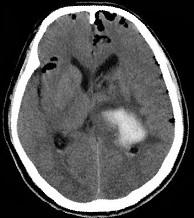

男,32岁,外伤后一天,CT检查如图,下面哪项诊断最恰当()A.脑膜瘤B.脑出血并颅内积气C.脑出血D.颅脑外伤E.颅内积气

问题 男,32岁,外伤后一天,CT检查如图,下面哪项诊断最恰当()

选项 A.脑膜瘤 B.脑出血并颅内积气 C.脑出血 D.颅脑外伤 E.颅内积气

答案 B